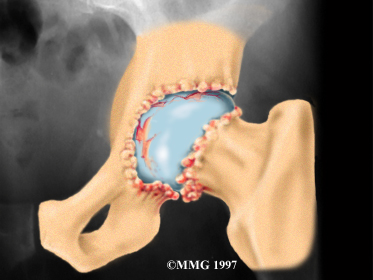

Articular cartilage is the smooth lining that covers the surfaces of the ball-and-socket joint of the hip. The cartilage gives the joint freedom of movement by decreasing friction. The layer of bone just below the articular cartilage is called subchondral bone. The main problem in OA is degeneration of the articular cartilage.

When the , or wears away, the subchondral bone is uncovered and rubs against bone. Small outgrowths called bone spurs or osteophytes may form in the joint.

The diagnosis of hip OA starts with a complete history and physical examination by your doctor. X-rays will be required to determine the extent of the cartilage damage and suggest a possible cause for it.

Your doctor will order X-rays to determine the extent of the cartilage damage and suggest a possible cause for it.